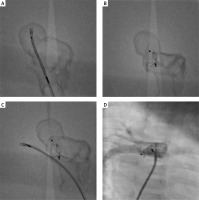

To choose the most optimal access, type, and size of device, we decided to simulate a malformation closure using a printed 3D model. Based on the CT scan of the heart, we prepared 3D printed models: model No. 1 was a solid print representative of a full volume heart and vessels anatomy (Figure 1 B), and model No. 2 was a hollow print for simulation representing chambers and vessels in the region of interest. Using model No. 2, made of semi-flexible material visible under fluoroscopy, we performed a simulation of malformation closure from the pulmonary artery with the 6 mm Amplatzer Duct Occluder I device. The position of the device was stable and did not hinder the free insertion of the catheter into the right pulmonary artery (Figures 2 A–C).

Figure 2

The simulated procedure from the femoral vein. 3D model limited to the region of interest – right pulmonary artery (RPA) is divided into 2 vessels. Malformation reservoir is visible. A – The sheath introduced from femoral vein to right pulmonary artery and malformation reservoir. B – Amplatzer ADO is implanted from pulmonary artery site. C – The sheath introduced to true right pulmonary artery. The implanted set does not narrow the right pulmonary artery. D – Control patient’s heart scan – implanted Amplatzer Vascular Plug II

Finally, from the right femoral vein, a 6 × 6 mm Amplatzer Vascular Plug II was implanted [1–5]. The final choice of an Amplatzer Vascular Plug was based on our belief that this device is more likely to provide the best treatment outcome, i.e. to close the fistula without residual leakage and to maintain normal flow in the right pulmonary artery. In control angiography, we did not find any flow disturbances in the right pulmonary artery (Figure 2 D). The fluoroscopy time was 6.2 min, and the radiation dose was 28 mGy. During the procedure we used Heparin 100 IU/kg. Due to the large reservoir and the lack of progressive standards, we recommended acetylsalicylic acid 5 mg/kg/day for 6 months.